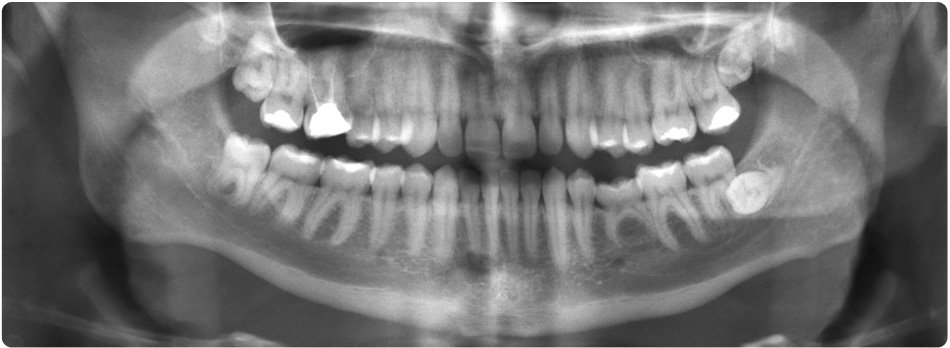

Many diseases of the oral cavity (which includes the teeth and surrounding tissues and bone) cannot be seen when t he dentist examines your mouth. An x-ray exam may help the dentist see:

- small areas of decay between the teeth or below fillings

- bone damage from a tooth infection (such as an abscess) or a cyst

- bone loss due to periodontal (gum) disease

- the position of unerupted teeth in children and adults

Finding and treating dental problems at an early stage can save time, money and unneeded discomfort and help prevent more serious health problems. X-ray images may be able to help the dentist detect damage and disease not visible during a regular dental exam.